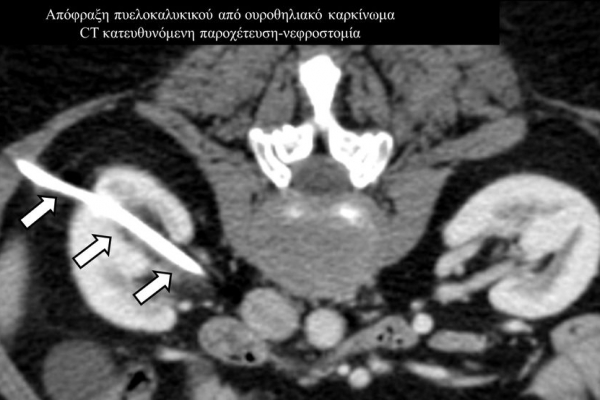

Η παρέμβαση διενεργείται υπό την καθοδήγηση αξονικού τομογράφου ή υπερήχων ή και με συνδυασμό τους. Ο επεμβατικός ακτινολόγος αρχικά αναισθητοποιεί την ανατομική περιοχή ενδιαφέροντος με τη χρήση τοπικής αναισθησίας και παρακεντεί την συλλογή διαδερμικά με λεπτή βελόνη. Στη συνέχεια μέσω ομοαξονικών συστημάτων συρμάτων-καθετήρων-διαστολέωντοποθετείται διαδερμικός καθετήρας τύπου pig-tail εντός της συλλογής, ο οποίος συνδέεται με εξωτερική παροχέτευση.